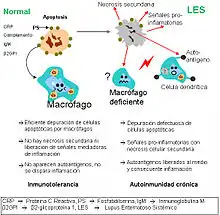

- Apoptosis: una de las alteraciones celulares más evidente en los pacientes con LES es un trastorno en el proceso de muerte celular denominado apoptosis, así como en el aclaramiento o eliminación de estas células apoptóticas. La expresión anómala de genes que regulan la apoptosis se ha asociado al desarrollo de enfermedades parecidas al lupus en modelos animales. En los humanos con LES se han demostrado trastornos de la regulación de la apoptosis en diferentes tipos de células, particularmente en linfocitos T y en la vía ligando Fas/FasL. En el lupus, durante la apoptosis, los autoantígenos sufren una notable redistribución, pasando a estar concentrados en las vesículas de la superficie de las células apoptóticas, con lo que determinantes antigénicos intracelulares, habitualmente ocultos, se hacen visibles para el sistema inmune. Además, existe un defecto en la fagocitosis y eliminación de las células apoptóticas y de los restos celulares, lo que origina la presencia mantenida de autoantígenos intracelulares, siendo así los restos apoptóticos una fuente de autoantígenos fundamental en el lupus.[41][42][43][44][45]

Los defectos en la depuración de células apoptóticas es una de las posibles explicaciones de ciertas enfermedades autoinmunes como el LES.

Los defectos en la depuración de células apoptóticas es una de las posibles explicaciones de ciertas enfermedades autoinmunes como el LES. - Autoanticuerpos: la producción de autoanticuerpos es un rasgo característico de los pacientes con LES. Su producción puede ser por activación policlonal de las células B o por estimulación inmune dirigida por autoantígenos.[47] Su importancia en el origen de la enfermedad se pone de manifiesto, por ejemplo, en el lupus eritematoso neonatal, que se piensa que es producido, al menos en parte, por el paso de los autoanticuerpos de la madre (anti-Ro y anti-La) al feto durante el embarazo, aunque también parece ser necesario un factor fetal complementario.[49] Además, los niveles del algunos autoanticuerpos llevan un curso paralelo a la actividad de la enfermedad y algunos se asocian con datos clínicos específicos de la enfermedad.[50]

- Autoanticuerpos e inmunocomplejos: los mediadores del LES son los autoanticuerpos y los inmunocomplejos que se forman con los antígenos. Los autoanticuerpos pueden estar presentes durante años antes de que aparezcan los primeros síntomas de la enfermedad.[51] Los autoantígenos que son reconocidos son presentados primariamente en la superficie de las células, particularmente por células activadas o bajo apoptosis, en las que los antígenos celulares han emigrado a la superficie celular, donde pueden ser reconocidas por el sistema inmune.[52] La fagocitosis y eliminación de los inmunocomplejos, de las células apoptóticas y de los restos derivados de las células necróticas son defectuosos en el LES, permitiendo la presencia de los antígenos y los inmunocomplejos durante períodos prolongados, haciendo que el daño en los tejidos vaya acumulándose hasta la aparición de la enfermedad clínica. Las células plasmáticas/células B que producen los autoanticuerpos están persistentemente activadas por el factor activador de células B (B lymphocyte stimulator o BLyS) y por las células T helper activadas, produciendo citoquinas como la IL-6 y IL-10.[21] También fallan en el LES los mecanismos de atenuación de estas funciones de las células T y B, incluyendo la generación de varios tipos de células T reguladoras y citolíticas y de sistemas atenuadores humorales idiotípicos.[48] Todos estos múltiples defectos originan una cascada de acontecimientos que comienzan con la anormal muerte celular y acaba en la célula B autoreactiva activada, proliferando y diferenciándose en células productoras de un exceso de autoanticuerpos frente a muchos antígenos nucleares. Además, y para complicar más la ya mala situación, se produce una activación del sistema inmune innato, con liberación de IL-1, TNF alfa, interferones, BLys y APRIL promoviendo la inflamación, además de la supervivencia de las células B autoreactivas. El resultado final es la producción de más anticuerpos antinucleares específicos, que pueden preceder a la manifestaciones clínicas durante años.[21]